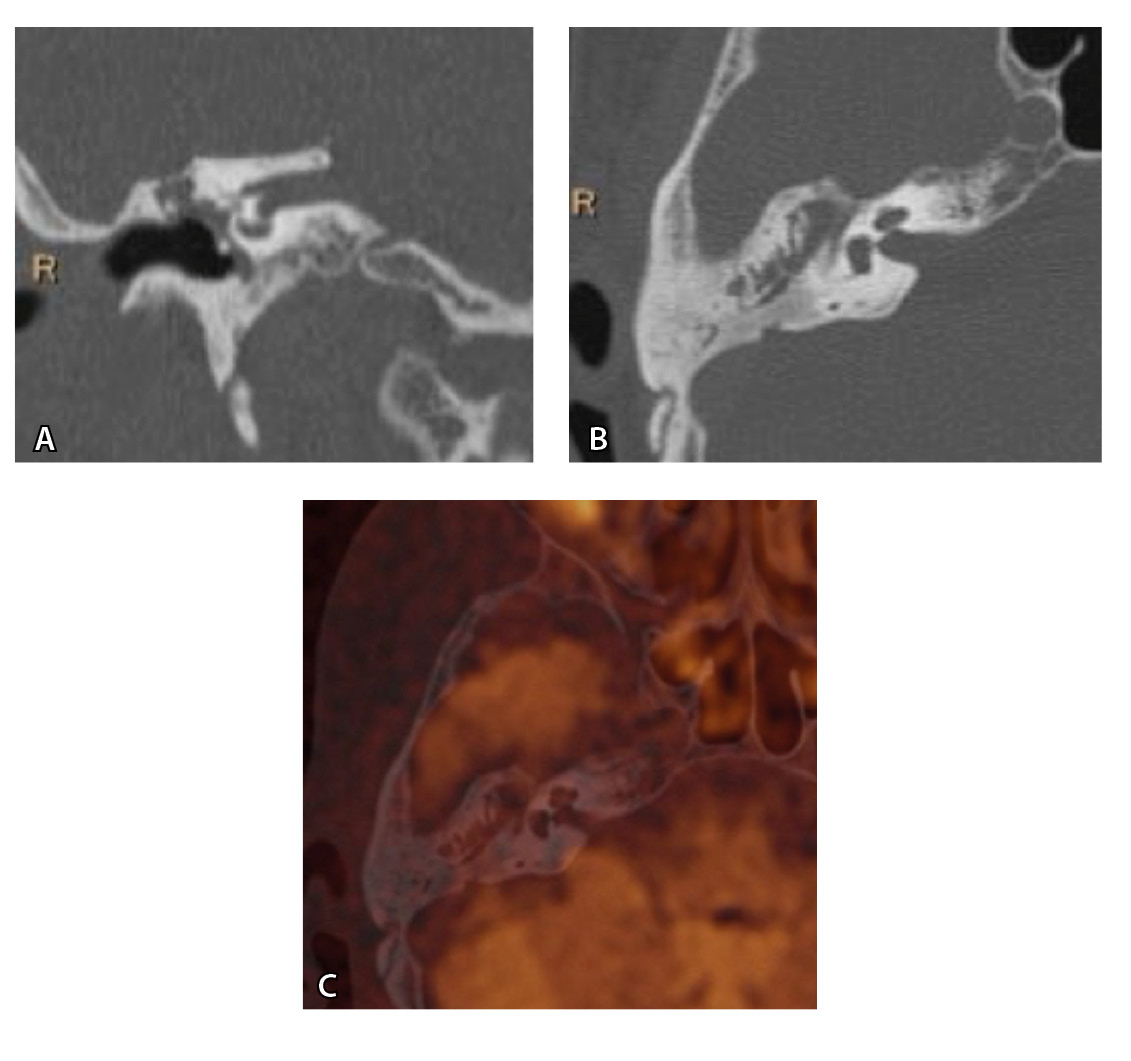

На рис. 3 и 4 показано расхождение данных КТ и МРТ.

Рис. 4. При компьютерной томографии (КТ) визуализируются признаки хронического гнойного среднего отита справа. Наблюдаются латерализация косточек среднего уха и узурация их по имедиальной поверхности на уровне эпитимпанума (тело наковальни и головка молоточка) – классические КТ-признаки холестеатомы натянутой части барабанной перепонки (А, Б). Однако по данным магнитно-резонансной томографии (В) и в последующем при оперативном лечении холестеатома не подтверждена